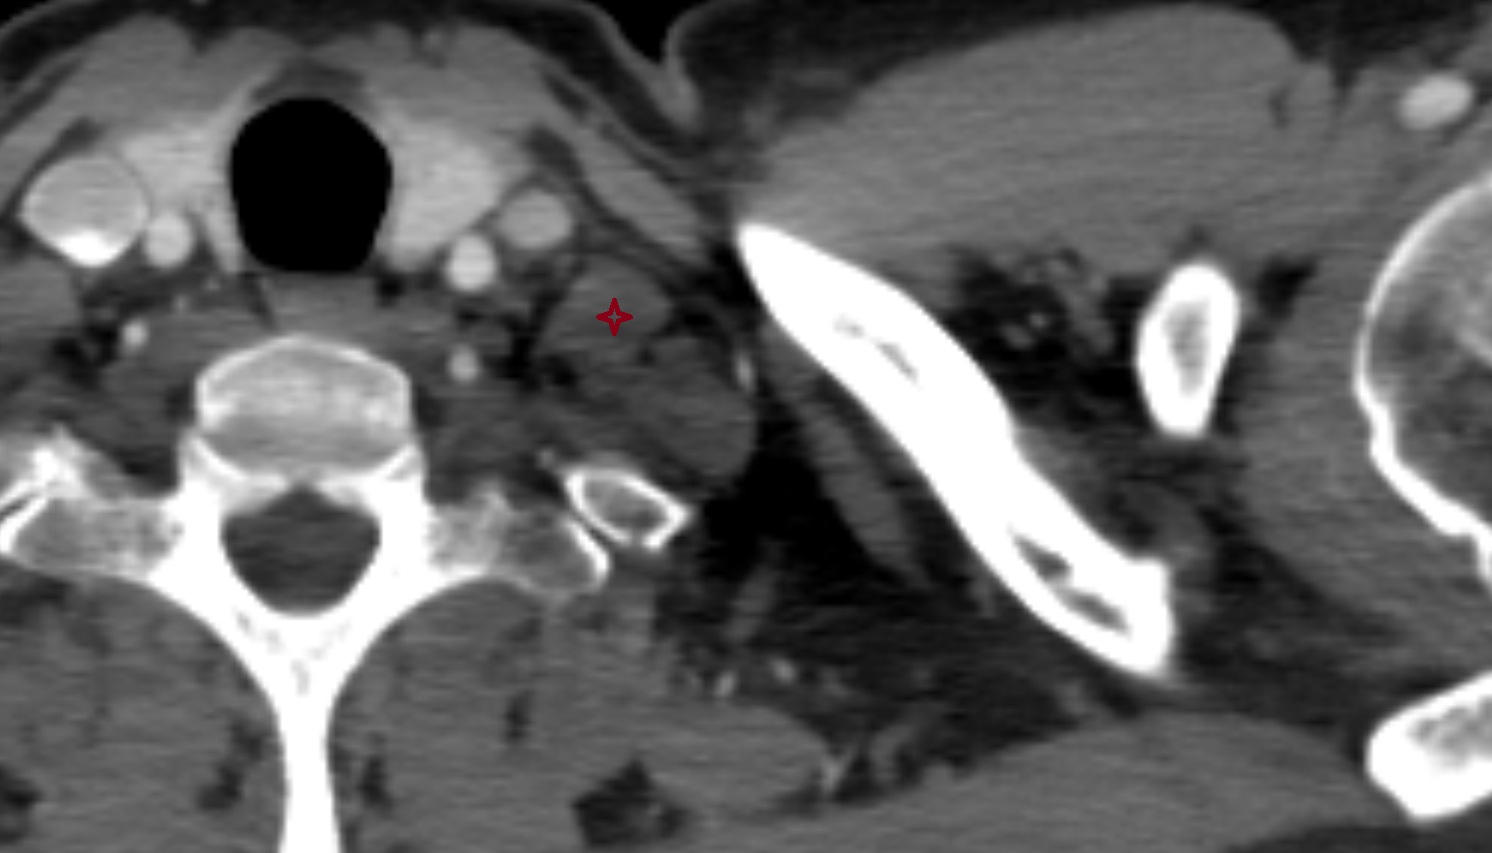

- Common carotid artery

- Internal carotid artery (cervical part)